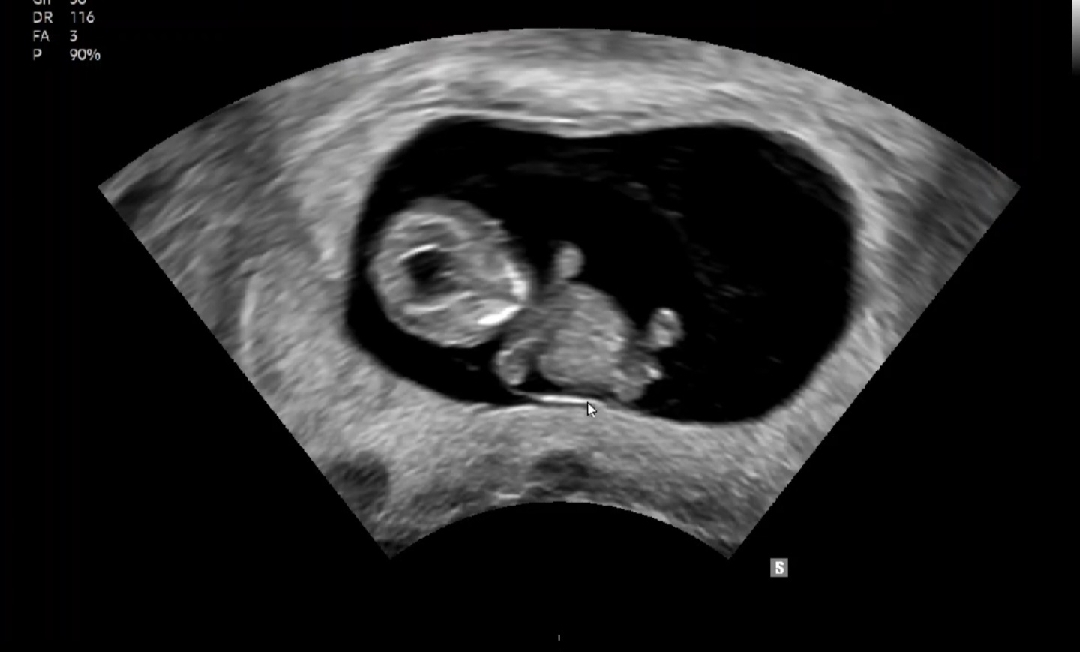

9주 6일♡

안녕하세요 :) 9주 6일차에요!!! 하리보가 파닥거리는거같고 너무 귀여워!!!!!요 애기집도 애기도 건강하게 잘 있어서 다행이에요 ㅠㅠ 3주뒤에 1차 기형아 검사도 예약되어있어서 걱정이에요 다들 얼마짜리로 검사 진행할 예정인가요?? 10만원대랑 50만원대가 있다는데..ㅠㅠ